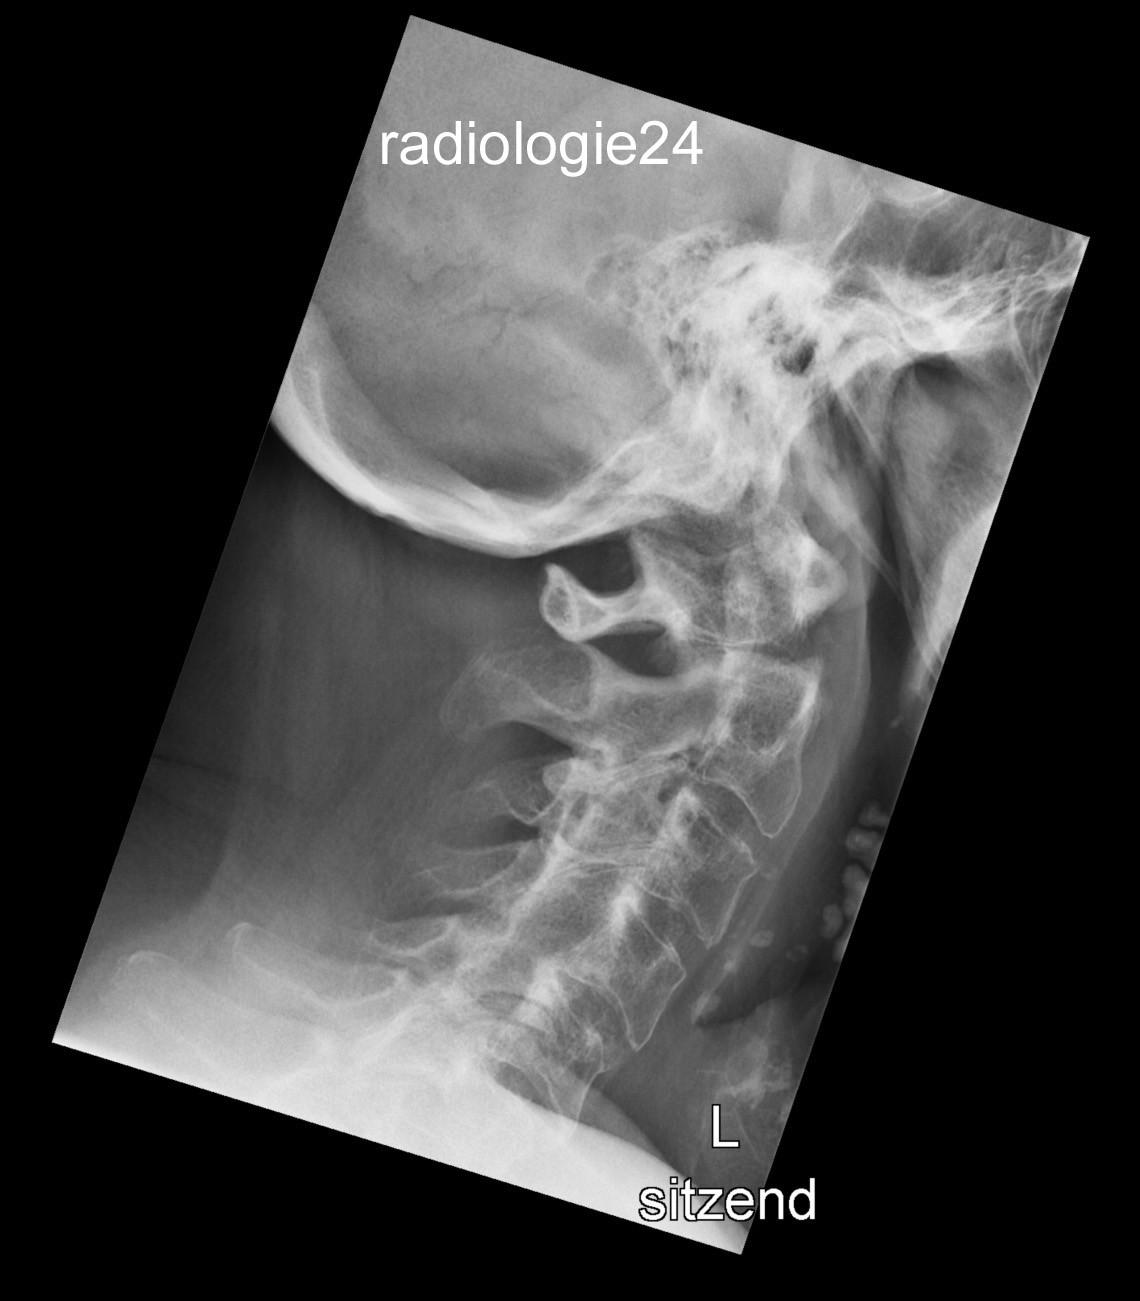

Röntgenfall des Monats Juli 2018 mit Auflösung

79 jähriger Patient Z.n. Sturz mit dem Velo auf den Kopf. Schmerzen HWS? Ihre Diagnose? Weitere radiologische Diagnostik?

Bild vergrössern

Link zur Auflösung mit ausführlichem Befund:

https://www.radiologie24.ch/radiologie-mediathek/roentgenfall_des_monats